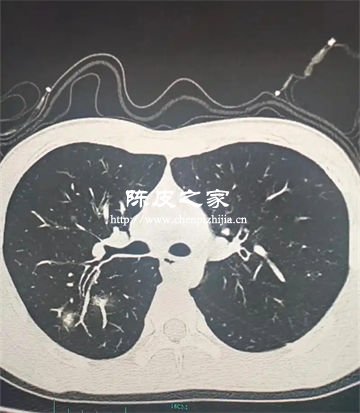

陈皮可以用来预防支原体肺炎吗

陈皮可能对预防支原体肺炎起到一定的辅助作用,但无法直接预防,预防支原体肺炎需要结合科学防护措施与规范医疗手段。